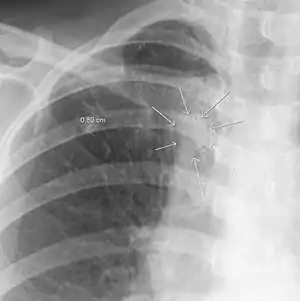

| The arrows denote an ill-defined nodular opacity in medial aspect of right upper lobe with ill-defined rim of lucency surrounding it | |

| Differential diagnosis | Aspergilloma |